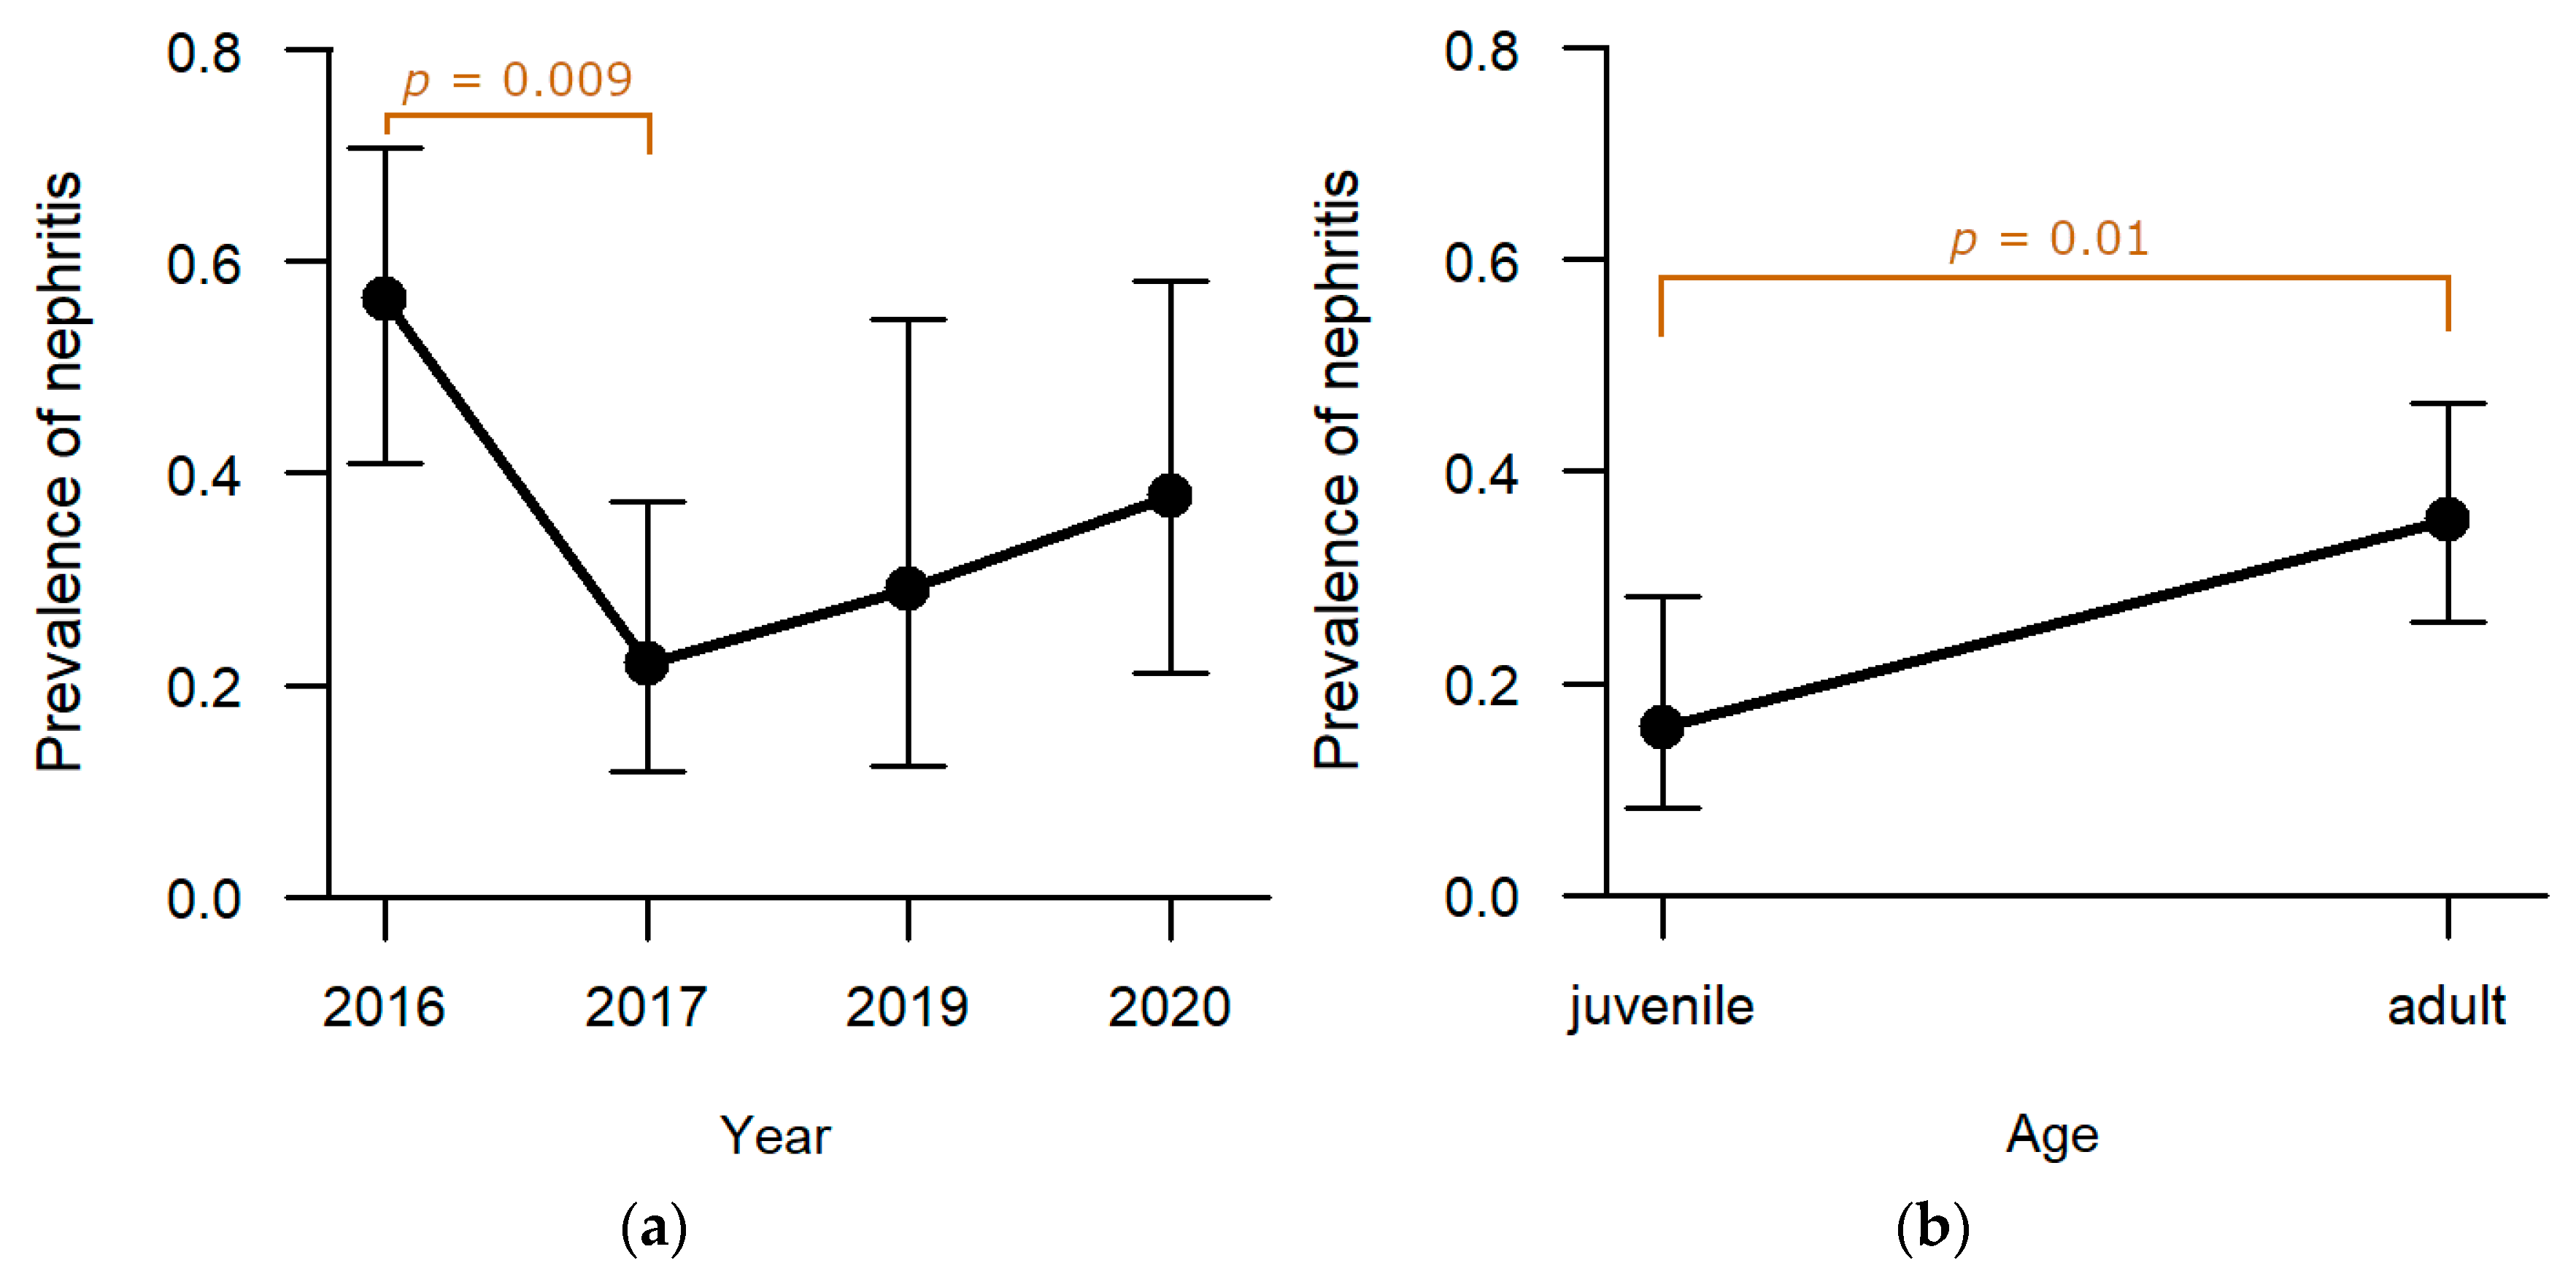

3.1.4. Urinary and Genital System

Kidneys: In one-third of the studied animals, inflammation of the kidneys was found (31.0%, n = 48). Whereas no significant effect of hunting ground or sex was observed, age (

p = 0.01,

Table S1) and sampling year (

p = 0.007,

Table S1) revealed a significant effect on the presence of nephritis. The prevalence of nephritis was the highest in 2016 (47.2%, n = 25;

Figure 11a), with significantly more hares confirmed in post-hoc analyses compared to hares sampled in 2017 (18.8%, n = 9,

p = 0.009;

Table S2). Between the other sampling years, no significant difference was determined in statistical analyses. Furthermore, significantly more adults were diagnosed with nephritis (37.6%, n = 38) than juveniles (18.5%, n = 10,

p = 0.01;

Figure 11b).

The pathomorphological findings of hepatitis and nephritis appeared to be age-related and were significantly more common in adults than in juveniles. Both findings were mainly diagnosed as chronic, non-purulent alterations and were already detected in deceased hares in this area with lower prevalence [

By analysing the impact of the sampling year, again, the two pathomorphological findings hepatitis and nephritis were detected significantly more often in 2016 compared to 2017 and for hepatitis also compared to 2020. The comparison of median serotitres for EBHSV showed a higher serotitre for 2016 compared to 2020. This indicates a more recent immune response to EBHSV in 2016. This might also explain the higher prevalence of hepatitis for this year. For the sampling year 2017, we cannot conclude any correlation, as we did not test specifically for EBHSV. Nephritis was previously detected due to infections with